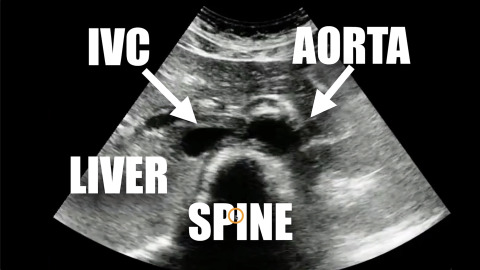

Ultrasound of Aortic Aneurysm

Dr. Avila reviews the ultrasound findings of aortic aneurysm.

1 chapterNovember 2019